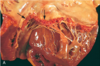

compare and contrast these…

leiomyoma or uterus

- well-differn tumor of bundles of smooth M cells that are VIRTUALLY identical to normal smooth M cells

adenocar of colon

- ca gland cells are irregular in shape and size and DO NOT resemble normal colon glands (top = normal, bottom = ca)

- differentiation b/c gland formation is seen

- invaded M layer of color